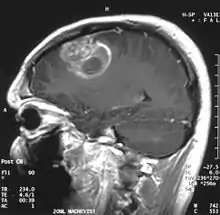

| Coronal MRI with contrast of a glioblastoma in a 15-year-old male | |

When viewed with MRI, glioblastomas often appear as ring-enhancing lesions. The appearance is not specific, however, as other lesions such as abscess, metastasis, tumefactive multiple sclerosis, and other entities may have a similar appearance.[53] Definitive diagnosis of a suspected GBM on CT or MRI requires a stereotactic biopsy or a craniotomy with tumor resection and pathologic confirmation. Because the tumor grade is based upon the most malignant portion of the tumor, biopsy or subtotal tumor resection can result in undergrading of the lesion. Imaging of tumor blood flow using perfusion MRI and measuring tumor metabolite concentration with MR spectroscopy may add diagnostic value to standard MRI in select cases by showing increased relative cerebral blood volume and increased choline peak, respectively, but pathology remains the gold standard for diagnosis and molecular characterization.